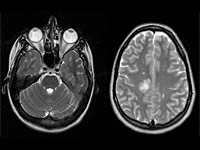

Análisis cerebrales pueden ayudar a predecir la psicosis